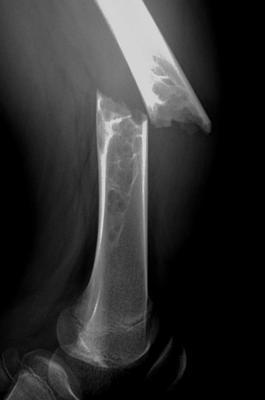

答:年轻人意外导致骨折,做了手术后,恢复挺好,但取了钢板后再次出现骨折。这是因为骨折愈合时,肢体通过内固定物实现力学传导,而骨折断端得不到应力刺激。临床愈合后,仍然达不到正常骨骼的韧度和硬度。当拆除内固定物后,激烈运动,或肢体不慎摔伤,或肢体不慎碰撞后,容易出现再次应力性骨折,骨折的部位往往在胫骨或股骨。

对喜欢运动的朋友来说,拆除骨折内固定物后3月,可以慢走锻炼、、太极拳、八段锦、游泳等,对抗性较小的运动是可以做的,当肌肉和关节得到锻炼,骨骼也相应结实。3月-6月后复查照片,如x线片提示骨折周围愈合出现骨的再塑造,内固定螺钉孔或髓内钉锁钉孔消失或缩小,此时,可以加强活动强度,如快跑、足球、骑车或蓝球等运动。术后一段时间,坚持补钙和维生素D,也有助于改善肌肉力量和预防再次骨折的。

如果是小腿(胫腓骨)轻微外伤导致骨折,要考虑有无先天性胫骨假关节,该类患者皮肤有典型牛奶咖啡斑,一旦骨折,不要尝试切开复位,容易造成骨不连,钢板内固定失效。我们团队近年也应用X-Uninon方法,ilizarov技术等整合方法,能有效的治疗先天性胫骨假关节。由于病人所在区域和报销比例问题,推荐去上海第六人民医院康庆林教授,湖南儿童医院梅海波教授等能胜任该病诊治的单位,进行规范诊治。